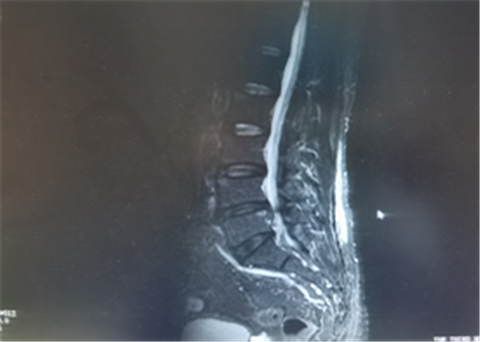

几个月前,50多岁的邱先生因腰部疼痛及左下肢麻木前来我院就诊,邱先生既往有十多年的“腰椎间盘突出症”病史,近日因工作时间太忙,长时间久坐及弯腰负重劳累,于是就出现了上述症状。为了进一步检查治疗,他来到我院门诊疼痛科就诊。 薛丁江接诊后告知患者,“虽然腰痛病史多年,但每一次因工作劳累诱发病情加重,治疗却效果欠佳甚至没有效果,就说明病情有可能加重了,最好能完善相关检查明确病情,这样治疗起来才会明确问题所在,了解病情的轻重”。 薛医生给患者检查后发现,患者腰部3-5棘突下软组织及左侧坚脊肌明显紧张,局部压痛(+),左侧直腿抬高试验(+)。完善腰椎MR检查后提示: 1.腰 4/5椎间盘脱出(中央型),腰5/骶1椎间盘突出(中央型)。2.腰3/4-腰5/能1椎间盘膨出、变性。3.腰5、骶1椎体相对缘终板炎。4.腰段椎管狭窄。5.腰部皮下水肿。6.腰椎退行性改变。 患者这次病情比之前有所加重,此次病情考虑由于腰椎间盘脱出压迫严重,且相应腰椎椎管有所狭窄,引起腰部疼痛及左下肢麻木表现。薛医生给邱先生解释了病情后,进行了小针刀松解及针灸理疗治疗,经过一个疗程的治疗,病情明显好转,皮下肿胀也恢复了,疗程结束1个月后回访时,患者已恢复健康。 1.腰椎间盘突出症是现如今引起腰痛的常见疾病之一,腰椎间盘脱出因为压迫周围软组织的情况较为严重,恢复的时间会比平常的腰椎间盘突出引起的腰痛稍微有所延长。早期可通过小针刀、针灸、中药及理疗等方式进行处理,大多数患者能得到比较好的恢复。 2.腰痛长期反复或者突发的患者建议完善腰部相关检查。不仅观察了病情的轻重,也排除了其他的恶性病情可能,医生也可以根据检查结果及症状进行综合判断病情的准确位置所在。 3.听从医生的建议。配合好日常生活的防护及注意事项,在病情恢复后,不要又立刻进行高强度工作及劳累。体质差一些的患者,有的需要多个疗程的调理治疗,就像汽车修理好了之后,没有加油提供动力支持,汽车运行起来还会容易出故障。 4.必要时手术治疗。腰椎间盘突出症,对于大部分患者来说,经过保守理疗治疗都能得到比较好的恢复,但对于小部分体质较差治疗效果欠佳的患者,经过三个月左右的治疗,效果还得不到满意,则可以考虑进行手术治疗。